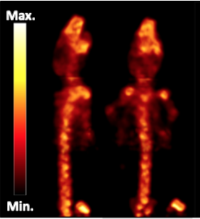

We're a spin-out from the University of Aveiro developing uniquely compact and affordable high-resolution PET systems. Our innovative scanning method allows high performance imaging while reducing complexity, weight and costs by more than 5 times, enabling a more flexible and broader use of this powerful technology.

EasyPET technology is a new concept for high-resolution PET imaging. Its simplicity allows overcoming the main barriers to the adoption and use of PET: high complexity and cost.

Entry-level preclinical PET scanner for small animal imaging research and training of medical imaging technologists.